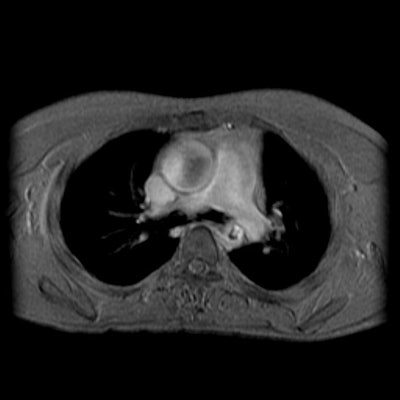

Post stenotic aortic dilatation

There is dilatation of the ascending aorta shown on the MR images below. The sinotubular junction is not affected. Flow void within the ascending aorta on flow images is related to turbulent flow associated with the stenotic aortic valve. The patient also has a coartation of the descending aorta. Turbulent flow void can be seen at the site of coarctation. About 50% of patients with aortic coarctation have a bicuspid aortic valve which can prematurely degenerate.